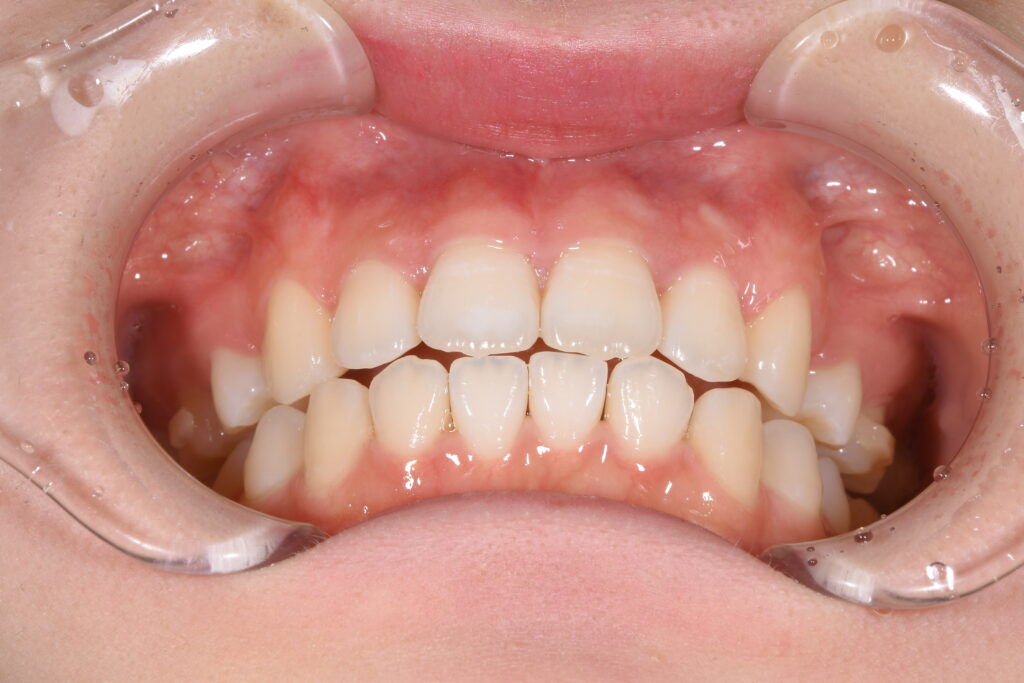

また、以下に装着時の写真を示します。

【インビザライン装着時】

【装置の写真・インビザライン】